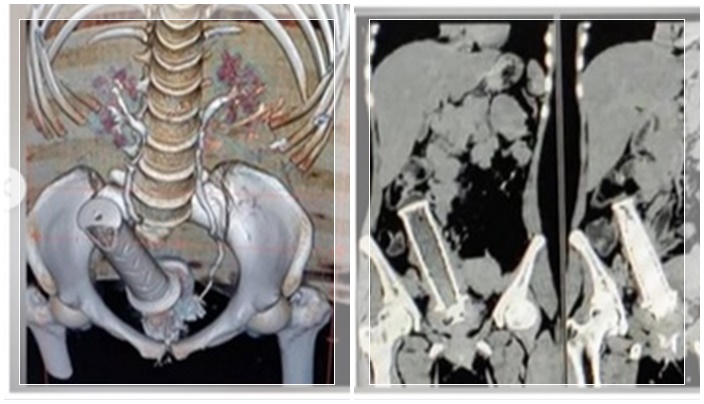

Saat menjalani pemeriksaan di RS MY Indore, tim medis menemukan benda logam yang menyerupai stang sepeda motor berada di area panggul, tepatnya di sekitar rahim.

Lokasi benda tersebut sangat berisiko karena berdekatan dengan organ vital lain seperti usus dan saluran kemih, sehingga berpotensi menimbulkan komplikasi serius.